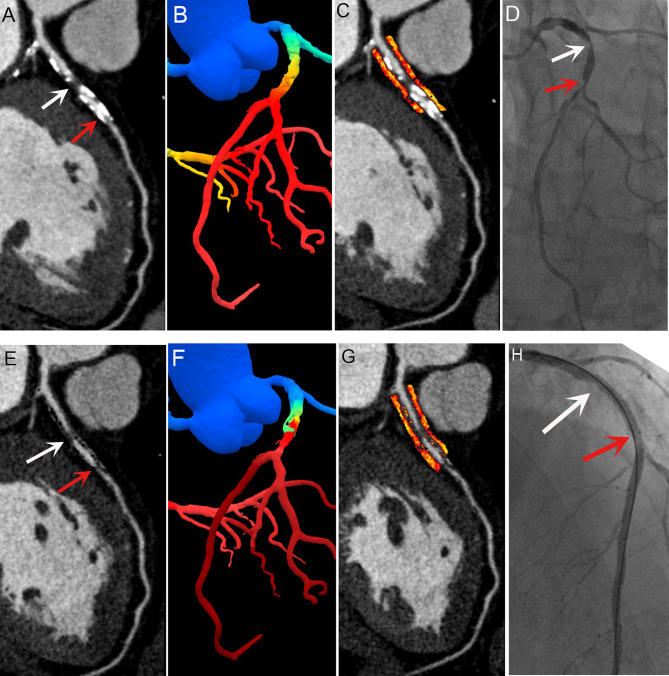

Subtraction fractional flow reserve with computed tomography and pericoronary fat attenuation index enhances the identification of revascularization needs in patients.